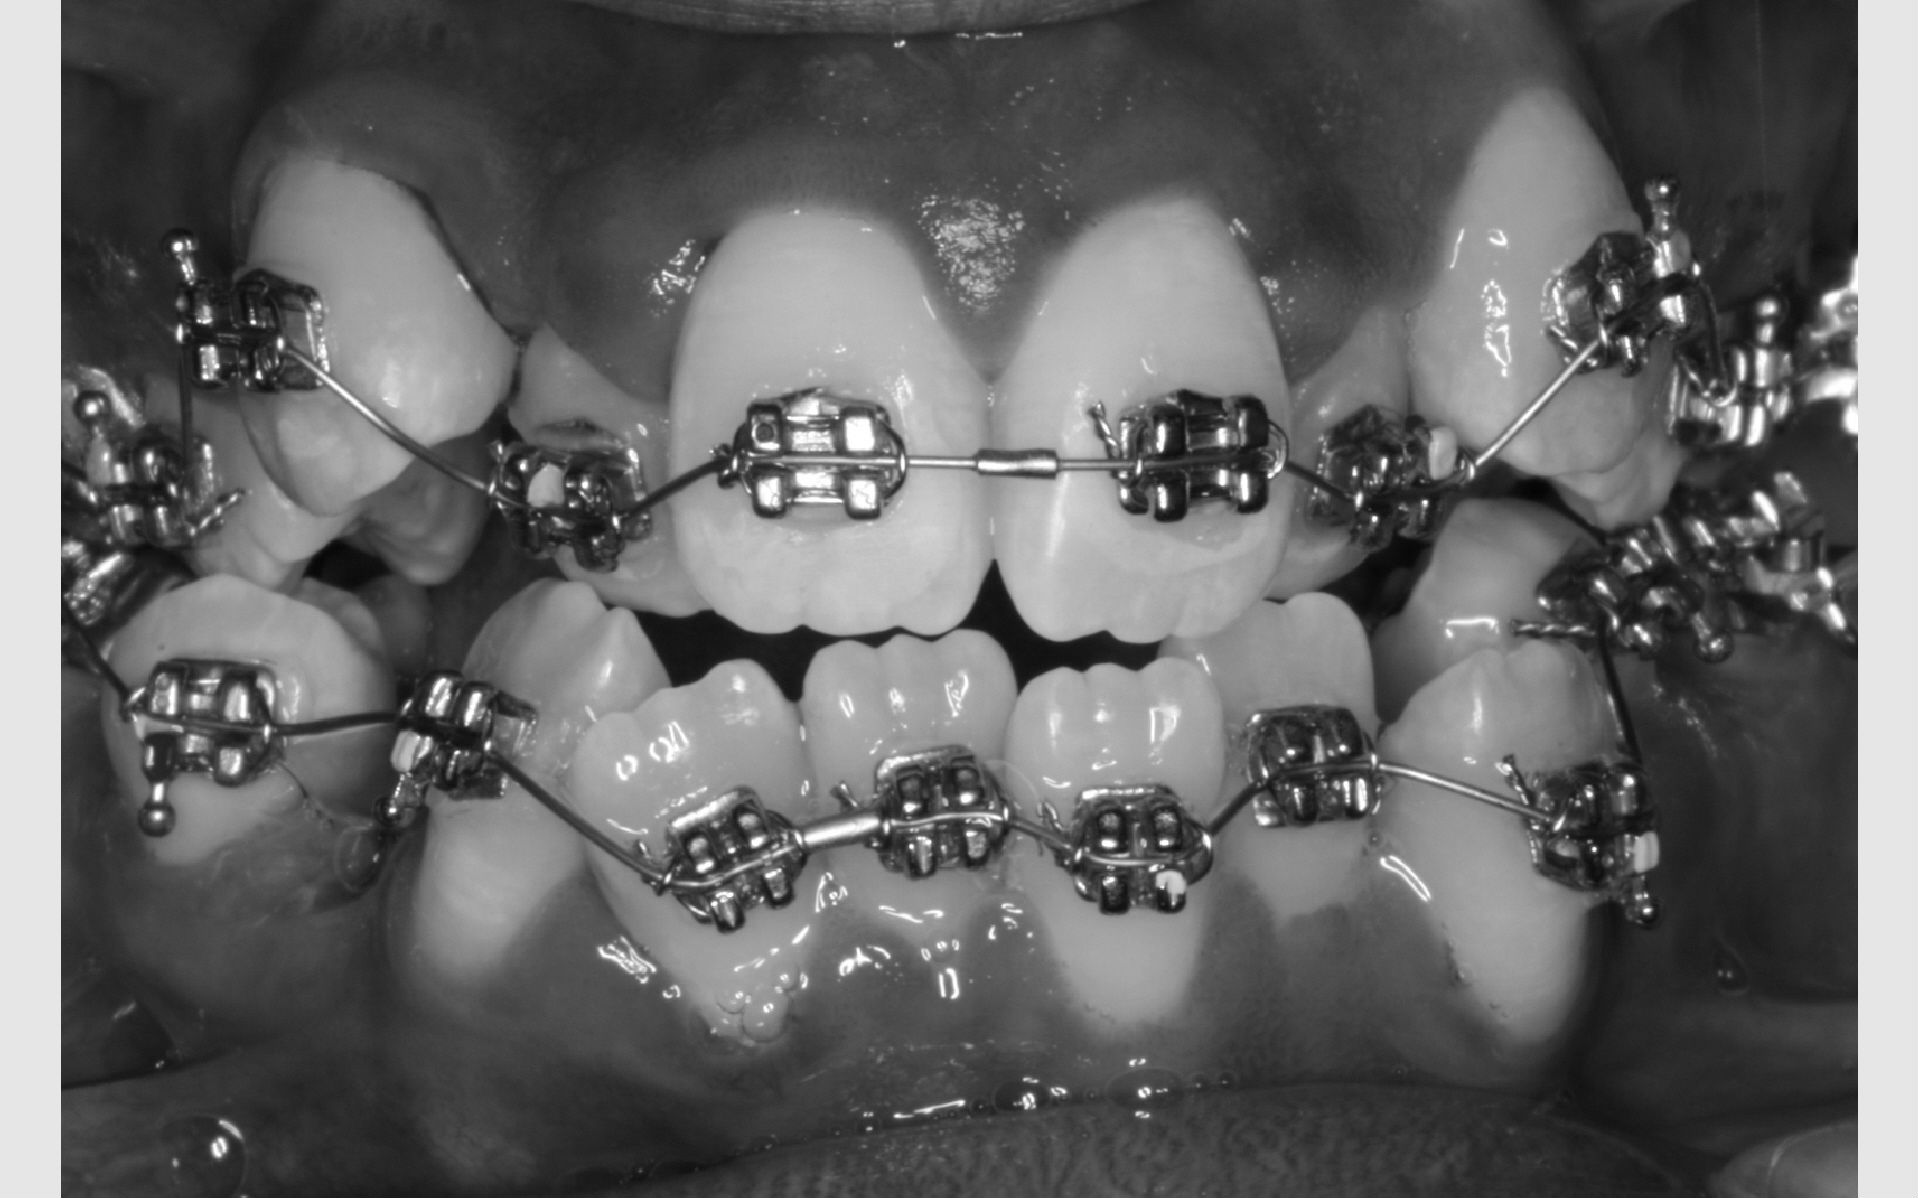

Ofte er der brug for fastsiddende bøjler på tænderne. Mange kalder dem "togskinner", hvilket er et passende navn, da tænderne nærmest bliver flyttet i et spor på den lås, der limes på tanden.

Det gør ikke ondt, men det tager lang tid at lime låsene på tænderne, da de skal sidde helt præcist. Så du skal være indstillet på at ligge i tandlægestolen i en times tid. Synes du, det lyder som lang tid, kan du tage høretelefoner på og høre musik samtidig.

Sådan bliver bøjlen sat på

Før låsene limes på, bliver tænderne pudset helt glatte. Herefter bliver overfladen gjort klar til limen med en blå gele, der skal ligge på tænderne i 30 sekunder. Der skylles med vand og blæses helt tørt, hvorefter låsene kan limes fat på tænderne. Limen er en form for plast, der svarer nogenlunde til den plast, man bruger til tandfyldninger.

For at plasten kan hærde, lyses der på tanden med ultraviolet lys i 20 sekunder. For at beskytte vores øjne mod det ultraviolette lys, bliver der holdt en orange skærm for øjnene. Når alle låse er limet på, forbindes de med en bue af metal. Det er den, der flytter på tænderne.

Kontrol af din bøjle foregår på Tandreguleringsklinikken cirka hver 6. uge. Det varierer lidt gennem behandlingen afhængig af, hvilken fase, du er i. Ofte bliver du bedt om at bruge nogle elastikker mellem bestemte tænder. Det er yderst vigtigt, at du følger det, der aftales fra gang til gang, så behandlingen går hurtigst og bedst.